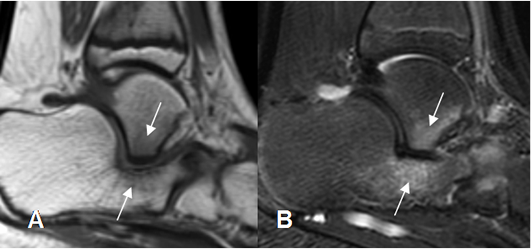

La RM es la modalidad de elección, para las valoraciones de las coaliciones fibrosas y cartilaginosas. (8). La calcaneonavicular se estudia mejor con las secuencias sagitales y axiales y la talocalcánea, con vistas coronales. (26).

Cuando se forman puentes óseos, hay continuidad de la medula ósea. En las coaliciones cartilaginosas y fibrosas, existe reducción de los espacios interóseos, formación de bandas hipointensas entre los huesos y edema trabecular asociado. (26). El edema trabecular ayuda mucho a sospechar el Dx, cuando se realiza una pruebas por otra indicación. (26). (Fig 139)

Fig 139. Coalición del tarso.

A: RM sagital en T1 y B: RM sagital en STIR. Coalición talocalcánea cartilaginosa, con edema óseo asociado.